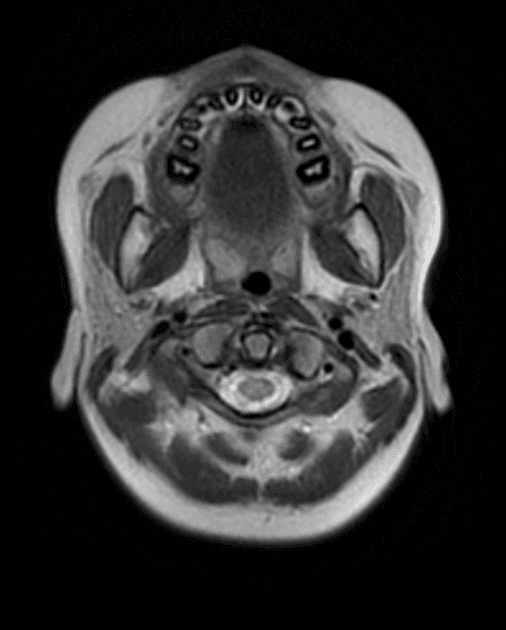

Xơ cứng rải rác

Bệnh nhân được chuyển đến để đánh giá theo dõi lại bệnh đã được chẩn đoán trong vài năm.

- Có nhiều tổn thương tăng tín hiệu trên hình ảnh T2/FLAIR ở vùng chất trắng vùng trên lều, trung não và cầu não, cả hai bên.

- Một số tổn thương định hướng vuông góc với não thất.

- Không thấy bắt thuốc bất thường.

Xơ cứng rải rác là một dạng mất bao myelin (demyelination) ở chất trắng có nguyên nhân chưa rõ. Các tổn thương có thể rải rác ở chất trắng vùng trên và dưới lều, cầu não, trung não và tủy sống.

Các tổn thương ở vùng septocallosal được coi là điển hình cho bệnh. Tủy sống cũng có thể bị tổn thương.

- "Xơ cứng rải rác thường biểu hiện bằng các tổn thương chất trắng quanh thất định hướng vuông góc với não thất (ngón tay Dawson)."

- "Việc không có bắt thuốc tương phản gợi ý bệnh đang trong giai đoạn ổn định hoặc không hoạt động."

- "Tổn thương thể chai và chất trắng cận vỏ não hỗ trợ chẩn đoán xơ cứng rải rác."